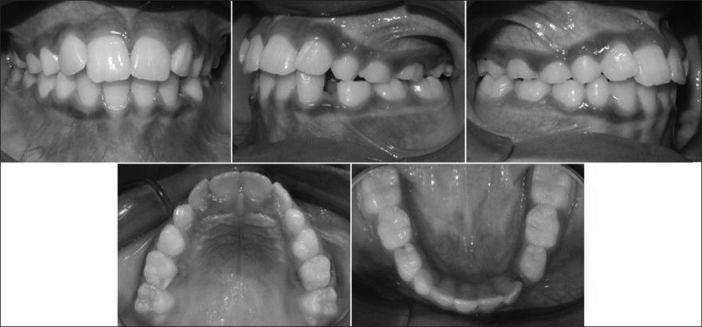

Most developing Class III patients display a retruded maxilla. Early intervention in mixed dentition is associated with better patient compliance and possibly a better orthopedic response, which can produce favorable results. The aim of this article is to present the fabrication of the new modified tandem appliance and its use in management of developing Class III malocclusion. The therapeutic results of a new modified tandem appliance are presented in an 8 year-old male patient with anterior cross bite and retrognathic maxilla at the mixed dentition stage. Anterior cross bite was corrected in 3 months and the positive overjet of 4 mm after continued use of the appliance for 1 year. There was a significant improvement in profile of the patient. The use of this appliance in this type of malocclusion enabled the correction of malocclusion in a few months and encouraging favorable skeletal growth in the future.

大多数处于生长发育期的III类患者表现出上颌后缩。在混合牙列期进行早期干预,患者的依从性更好,并且可能获得更好的矫形反应,从而产生良好的效果。本文的目的是介绍新型改良串联矫治器的制作及其在生长发育期III类错牙合畸形治疗中的应用。本文展示了一名8岁男性患者在混合牙列期使用新型改良串联矫治器治疗前牙反牙合和上颌后缩的治疗结果。3个月内前牙反牙合得到矫正,继续使用矫治器1年后覆盖达到4mm的正值。患者的侧貌有显著改善。在这类错牙合畸形中使用该矫治器,能够在几个月内矫正错牙合,并有望在未来促进有利的骨骼生长。